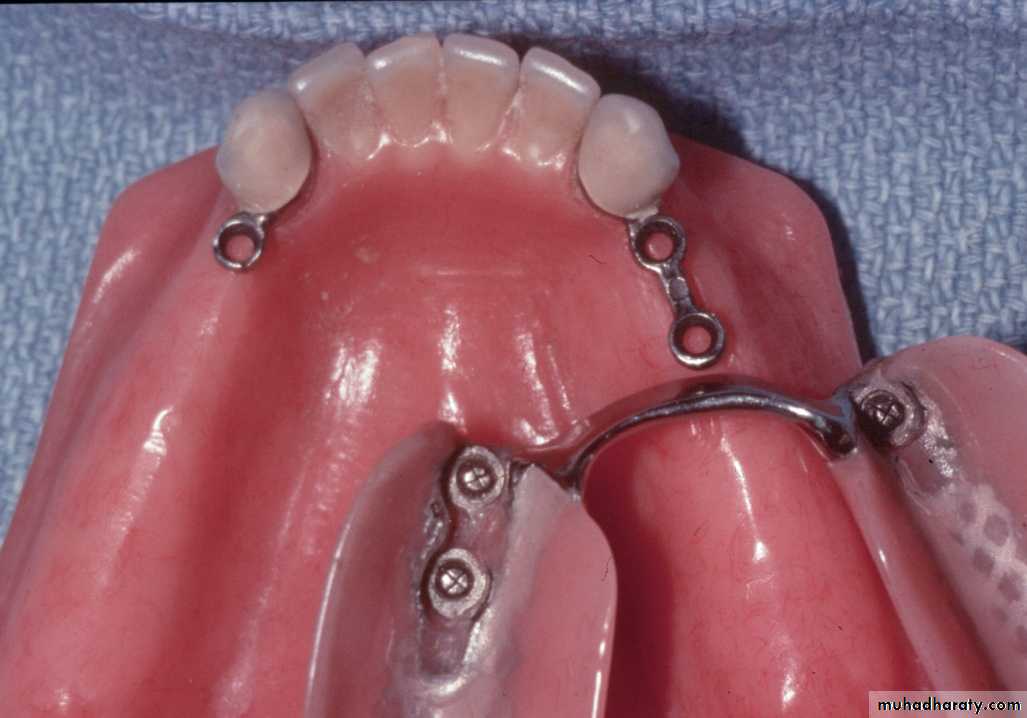

UNFAVORABLE ATTACHMENT APPLICATION:Stud Attachments

►Snap fasteners, mainly used for overdenture support, retention & stability.

► They consist of two main components:

Definition of stud attachments

Male projection

Female part► The two components interlock to form a retentive unit, mechanically attaching the superstructure to the abutments.